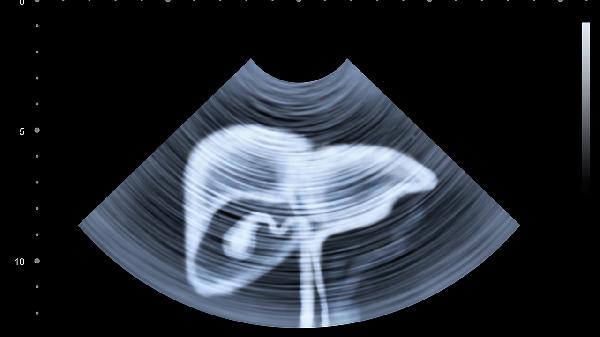

③春季体检建议加做肝脏超声和甲胎蛋白检测